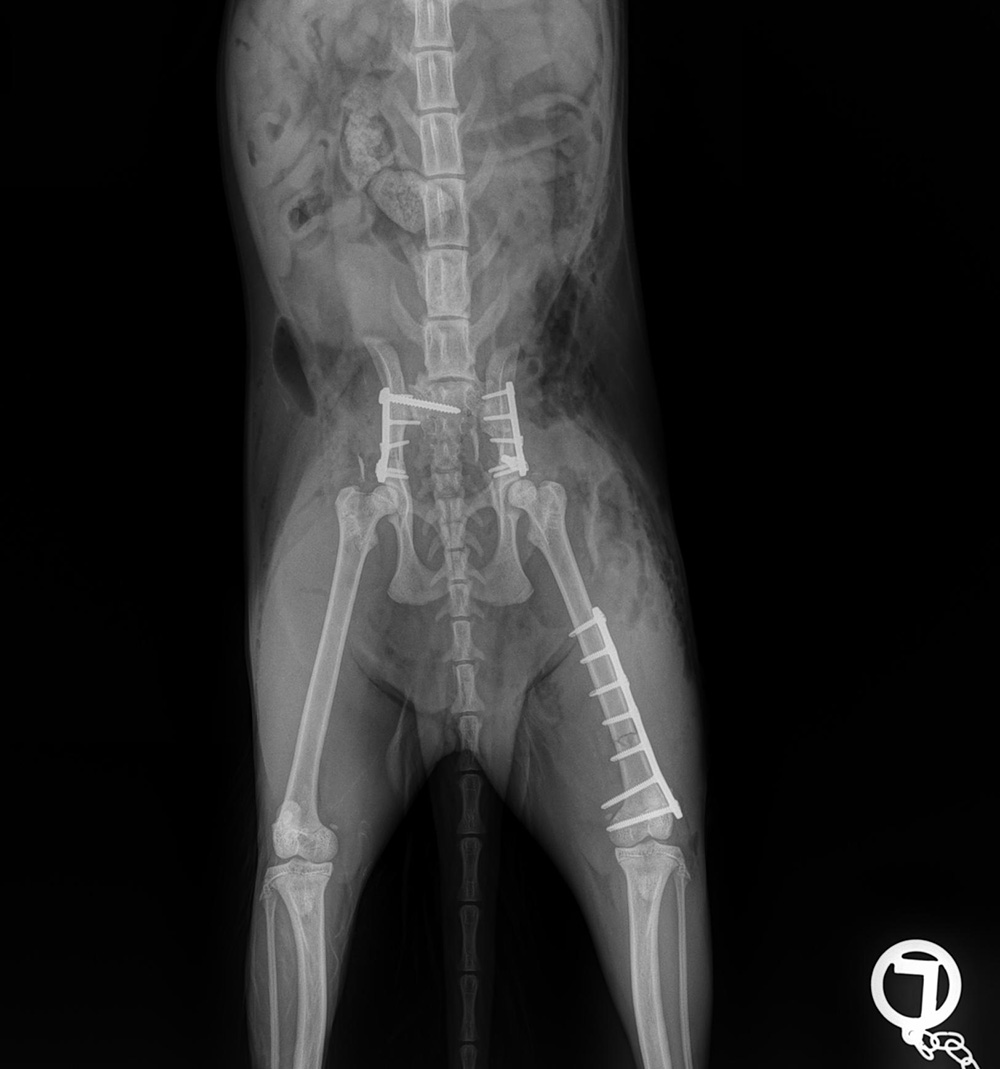

The course will include- fracture analysis and planning based on evidence in biology of fracture healing and the different implants.

- ‘biologic plating’ or rigid fixation? When and what

- bridging plates: advantages and dangers.

- bone by bone, tips and problems (humerus, radius/ulna, femur, tibia, pelvis)

- complications with implants and infections.

- Review of foundations of fracture repair

- Application of locking plates

- Decision making in fracture repair- for various cases

- Dealing with complications